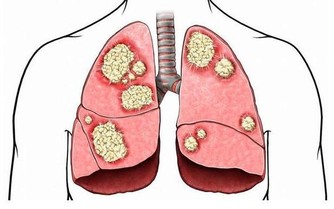

10.增強心肺功能:只要簡單地走路、讓你在過程中的呼吸頻率提高,就能血液中的氧氣更快速流動、排除代謝物質、還能讓自我療癒能力更好。